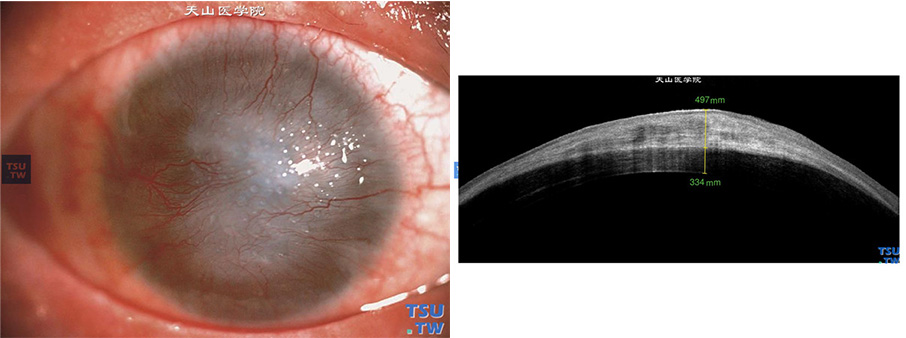

结角膜干燥:患者几年前因药物过敏,导致全身皮疹,角膜被新生血管膜覆盖,角膜基质形成瘢痕;RTvue OCT检查,角膜明显水肿增厚,角膜基质层内可见致密的、密度不均的影像,角膜上皮层欠完整